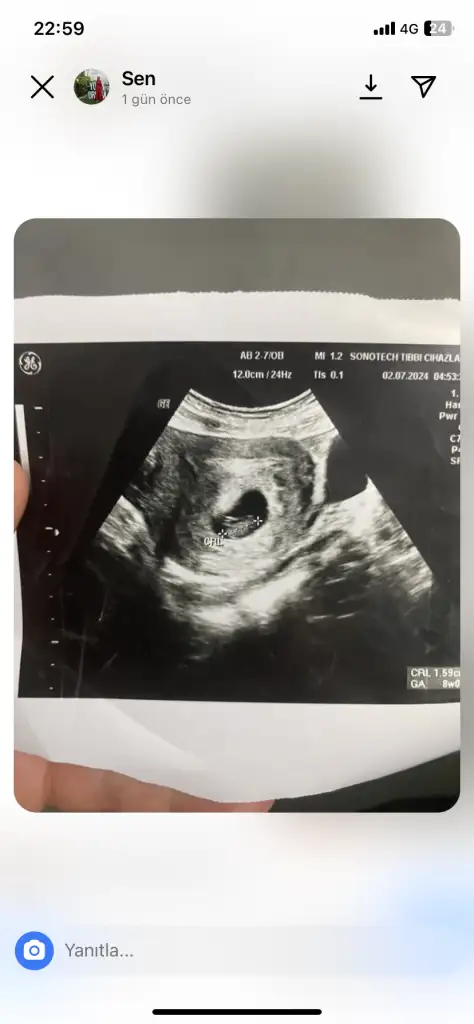

Alttan bakıldıysa kız ustten bakıldıysa erkek benceMerhaba ben Kanada’da yaşıyorum ve 8 haftalık hamileyim, keseye göre cinsiyet tahmini yapabilecek var mıdır, bu ülkede çok geç söylüyorlar şimdiden dayanamıyorum :))

Kızımın kesesine benziyor..Sağlıkla gelsinMerhaba ben Kanada’da yaşıyorum ve 8 haftalık hamileyim, keseye göre cinsiyet tahmini yapabilecek var mıdır, bu ülkede çok geç söylüyorlar şimdiden dayanamıyorum :))

8 haftalık karnımdan. BakıldıKaç haftalık? Ve alttan mı ustten mı bakıldı?